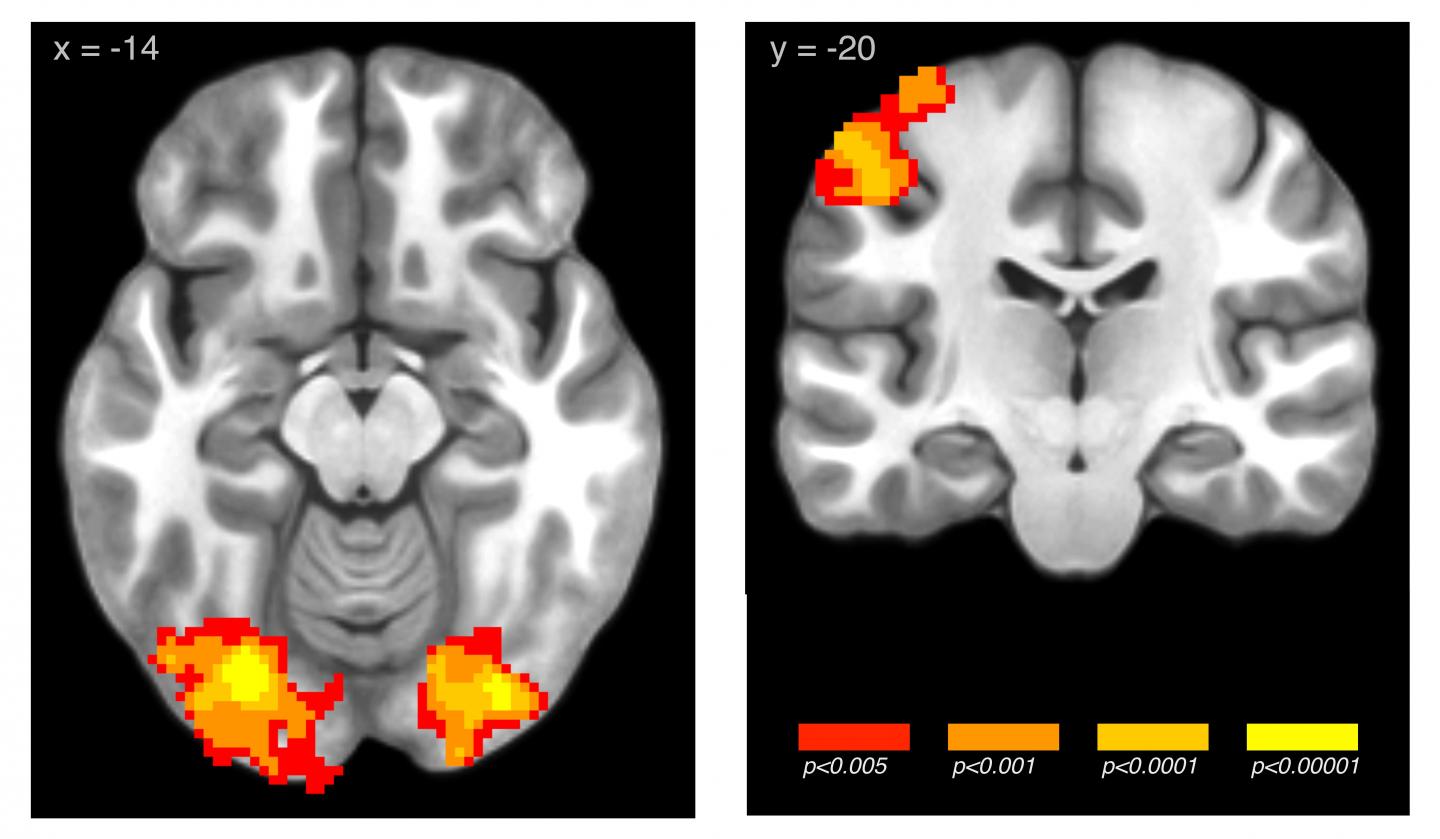

Elliott Wimmer and colleagues found that men and women better retained arbitrary associations between pictures of landscapes and monetary gain when they learned the associations in short sessions spaced out over weeks compared to a single, 20-minute session. The researchers' neuroimaging data reveal that training led to greater engagement of learning-related regions of the brain. each type of learning engaged different parts of the brain. These results provide a starting point for exploring how learned associations that have negative effects on human health and wellbeing, as in addiction, could be unlearned.

Article: Reward learning over weeks versus minutes increases the neural representation of value in the human brain*